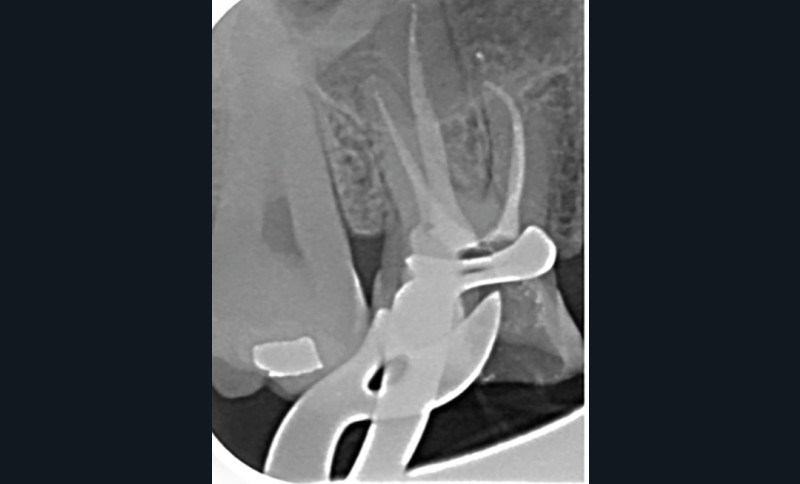

Perforation infra-osseuse avec accès visuel direct (fig. 3)

Ce type de perforation est également la plupart du temps iatrogénique et survient lors de la recherche ou de la mise en forme canalaire, lors de la préparation pour un logement de tenon radiculaire. Situées au niveau du plancher pulpaire des dents pluriradiculées, ou au niveau des entrées canalaires des dents monoradiculées ou pluriradiculées, il s’agit le plus souvent de perforations à quatre parois. Si la perforation survient en cours de traitement, elle doit être gérée immédiatement pour un meilleur pronostic (fig. 4). Néanmoins, il est important de prendre en compte l’épaisseur résiduelle du plancher. Si le plancher est trop fin, il ne sera pas possible d’envisager de traiter la perforation.

Les étapes 1 à 7 sont similaires à la situation 1.

Protocole pour la gestion d’une perforation du plancher avec la technique du tunnel (cela n’est réalisable que si le plancher est présent en épaisseur suffisante, ce qui n’est pas nécessairement le cas lors de perforations iatrogènes) :